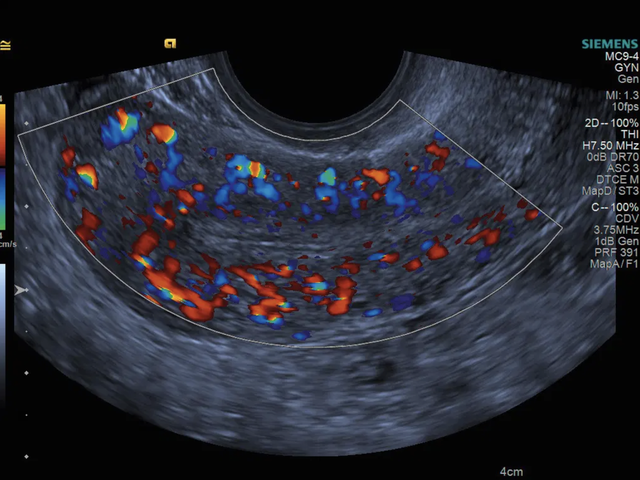

- MC9-4 (4 - 8 MHz)

Ендовагінальне сканування матки у кольоровому доплерівському режимі за допомогою датчика MC9-4